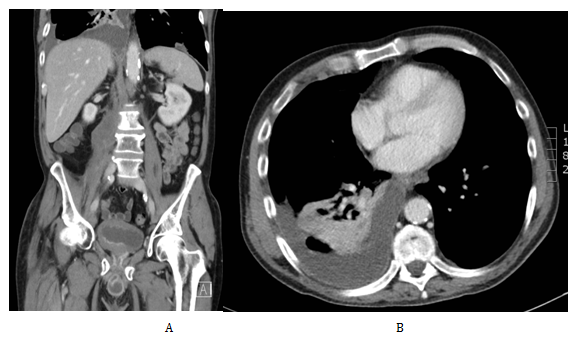

Following the completion of his radiotherapy he presented early in clinic after 2months with two malignant deposits at the base of his penis at the left side. At that stage he was offered palliative chemotherapy with cisplatin and pemetrexed. He had 6 cycles in total. Immediate cross sectional imaging showed disease regression. However, this was a short lived response as he subsequently developed an enlarging mass on the base of his penis; this was treated with another 5 fractions of radiotherapy. Subsequent CT scans (Figure 4) confirmed progression of disease with new pulmonary metastasis, pelvic and hilar lymphadenopathy and metastasis in the right psoas and T3. He had another 2 cycles of carboplatin and pemetrexed chemotherapy which was discontinued as there was no clinical improvement. He was at that point referred to the palliative team for symptomatic treatment. At the later stages of his disease, he developed an enlarging fungating tumour in the base of the penis which was his primary source of discomfort. This was discussed in our tertiary centre and was felt that penectomy and wound debridement would create significant wound management problems and thus was not attempted. He passed away on the 37months after his initial presentation.

Figure 4 Cross section topographic images of recurrence in the right psoas muscle (A) and pulmonary metastasis in the transverse plane (B).